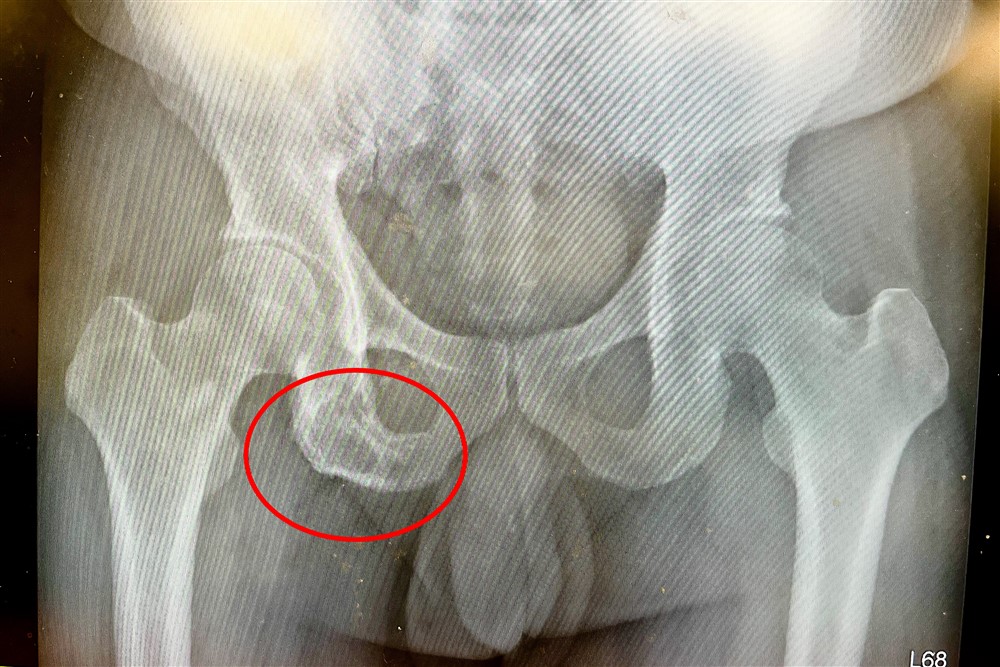

影像檢查顯示坐骨骨頭已被侵蝕。

白先生的電腦斷層檢查影像發現坐骨骨頭被侵蝕的病灶,轉診到台中慈濟醫院血液腫瘤科。黃冠博醫師抽血檢驗多項腫瘤指數都是正常,進一步做血液蛋白質免疫電泳分析,發現血清中的單株球蛋白濃度異常升高,再經由骨髓切片檢查,確診為「多發性骨髓瘤」造成的骨骼病變與「單株丙型免疫球蛋白血症」。